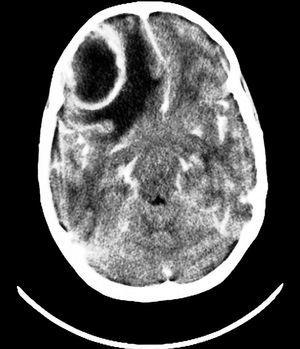

Niña de 11 años que presenta episodio de desviación de la cabeza y comisura bucal a la izquierda con movimientos clónicos del brazo derecho y revulsión ocular de pocos minutos. Asocia cefalea holocraneal. Había sido diagnosticada 10 días antes de sinusitis maxilar tratada con amoxicilina-ácido clavulánico. Esa mañana había ido al otorrino que le trata con metilprednisolona y le cambia la antibioterapia a ciprofloxacino. En la exploración destaca un enrojecimiento y edema de párpado derecho. En la analítica presenta 9.700 leucocitos/μl (granulocitos 61 %); PCR, 8,2 mg/dl; VSG, 76 mm/h. Se realiza TC craneal encontrándose sinusitis frontoetmoidal maxilar derecha. Es ingresada con amoxicilina-ácido clavulánico i.v. Al día siguiente se realiza RM: sinusitis frontoetmoidal maxilar derecha, engrosamiento dural frontal derecho y absceso incipiente frontal derecho. El EEG muestra actividad de ondas lentas irregulares en región frontal derecha. Se cambia tratamiento antibiótico a: cefotaxima, vancomicina y metronidazol, instaurándose medicación antiepiléptica con valproato. A los 16 días de ingreso comienza con cefalea, vómitos y deterioro del estado general por lo que se realiza TC que demuestra un aumento del tamaño del absceso frontal derecho con edema y efecto masa. En la RM presenta absceso frontal derecho de 2,5 cm (fig. 2). Se realiza drenaje del absceso. A las 4 semanas presenta, coincidiendo con administración de cefotaxima, una reacción urticarial, sustituyéndose por ciprofloxacino.

Figura 2.RM craneal: absceso frontal derecho (captación en anillo). Caso 5.